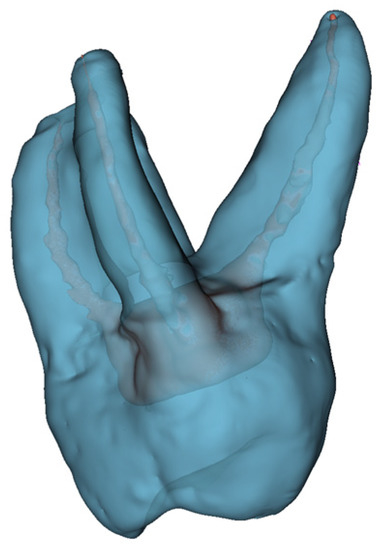

In the first case, the patient was referred to endodontic treatment, while in tooth 17, carious pulp exposure was detected. It was a deep subgingival carious lesion. Thus, the patient considered extraction and implant placement, and as a consequence, the patient was referred for microCBCT. Upon analyzing the scans together with the patient, a decision was made to perform endodontic treatment. On the CT performed, four roots with canals of significant curvature are visible. All four canals were chemomechanically prepared and filled. Finally, the endodontic treatment was successful. The procedure was performed without any complications thanks to the high accuracy of recognition of the course of all four tooth canals. The 3D of tooth 17 with carious pulp exposure was shown in Figure 8.

Figure 8. The 3D of tooth 17 with carious pulp exposure.

Prior to starting endodontic treatment, it is necessary to conduct a thorough diagnosis to assess the anatomy of the tooth and the condition of the periapical tissues. In addition to the intraoral examination and history taking, an X-ray examination is necessary to make a proper diagnosis and to plan treatment. A two-dimensional X-ray is not always sufficient. Especially in the case of re-treatment, cone-beam computed tomography has a greater diagnostic value. Thus, this paper evaluated the application of mixed reality for root canal treatments due to its complex nature. The created 3D model, which is shown in Figure 8, is helpful at the first stage of treatment when locating canal orifices. Thanks to the visible curvature of the roots, dentists can choose tools that will be able to bend at the right angle around the root tip. In the case of hand and nickel-titanium rotary files, it is possible to bend the tip of the tool at an appropriate angle. Thanks to the possibility of the simultaneous assessment of canal curvatures in all planes, it is also possible to choose the right file insertion path for each canal. The results obtained show that the analysis of 3D holograms takes about 52% less time than the analysis of computed tomography scans. The significant advantage of the proposed approach is the fact that in one image, the entire tooth and the anatomy of its canals are visible, while the CBCT is not able to provide the entire internal structure of the tooth at the same time.